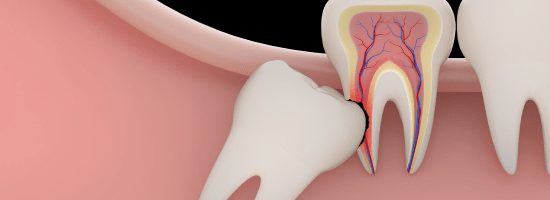

Removal of Impacted(Wisdom) Teeth

Impacted teeth, especially third molars (wisdom teeth) or canines, are those that fail to erupt properly and remain buried in the jawbone. These teeth are surgically removed by an oral surgeon to prevent pain, infection, or misalignment of surrounding teeth.